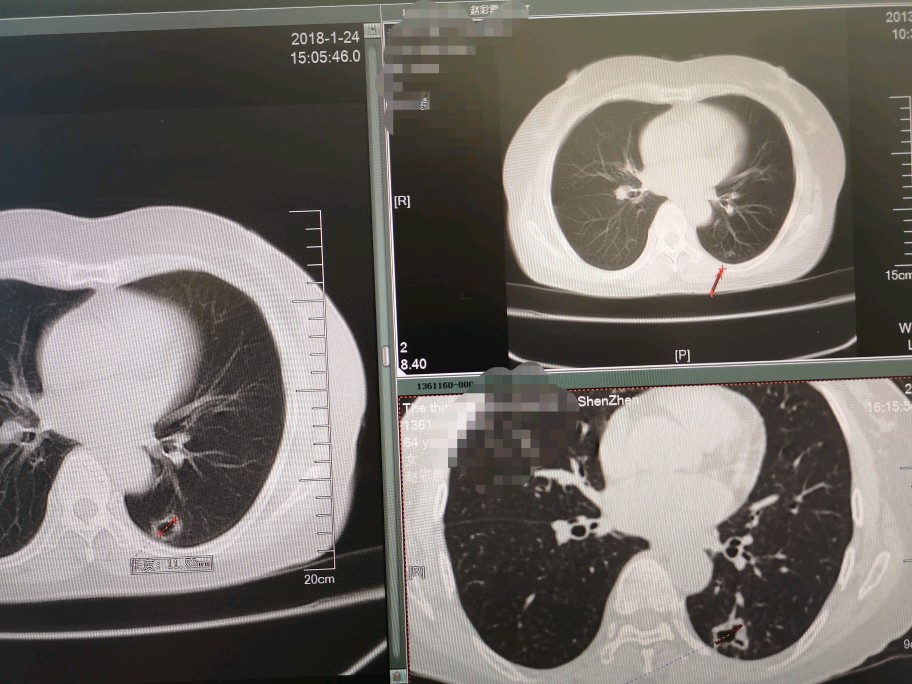

张阿姨(化名)5年前因咳嗽,确诊右上肺肺结核,按医生嘱咐坚持服用了一年的抗结核药物。一年后复查CT发现原来左下肺的小结节变成了小空洞,全面检查没有发现活动性肺结核依据,医生建议继续观察。连续三年肺部CT检查发现左下肺空洞逐步增大,壁较前增厚。张阿姨停药后一直没有咳嗽、咳血、消瘦等症状,平时注意锻炼身体,坚持每年体检。PET/CT提示左下肺空洞呈高代谢,肺门、纵膈淋巴结阴性,考虑周围型肺癌。

哪些病会表现为气囊?肺大疱、先天性囊性病变、结核和肺真菌病,以及肺癌、金葡菌感染等。由于肺癌晚期生存时间短,早诊早治是关键,发现肺内有肺大泡或肺囊肿,特别是“囊泡壁厚薄不均,囊内有细小分隔或血管影等征象”,务必加强随访,如果随访过程中出现囊腔扩大、囊壁局部或整体增厚、局限壁结节或外周肿块形成、腔内间隔、外壁毛刺或晕轮征等征象时要高度怀疑“囊性肺癌”的可能性。

关于囊性肺癌形成原因,一般认为癌瘤生长在小细支气管壁上,随着生长瘤体增大,使管腔完全阻塞,造成远端肺泡膨胀破裂,形成肺囊腔,癌组织支气管壁侵入囊腔形成壁结节影。